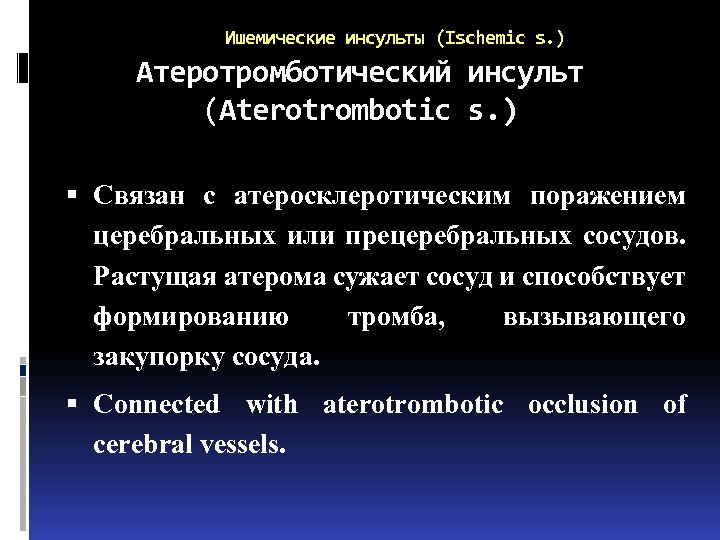

Ишемические инсульты (Ischemic s. ) Атеротромботический инсульт (Aterotrombotic s. ) Связан с атеросклеротическим поражением церебральных или прецеребральных сосудов. Растущая атерома сужает сосуд и способствует формированию тромба, вызывающего закупорку сосуда. Connected with aterotrombotic occlusion of cerebral vessels.

Ишемические инсульты (Ischemic s. ) Атеротромботический инсульт (Aterotrombotic s. ) Связан с атеросклеротическим поражением церебральных или прецеребральных сосудов. Растущая атерома сужает сосуд и способствует формированию тромба, вызывающего закупорку сосуда. Connected with aterotrombotic occlusion of cerebral vessels.